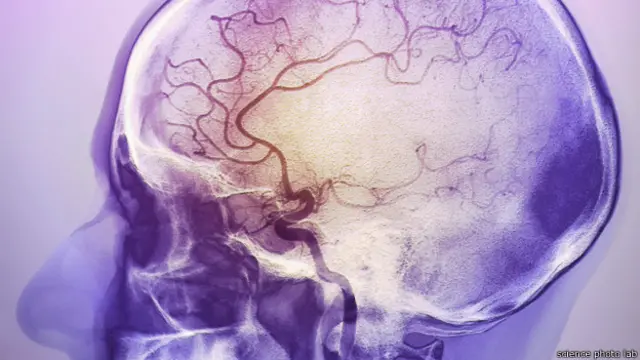

ख़ून के थक्के बनने या मस्तिष्क में रक्तस्राव होने से भी दौरे पड़ते हैं और इससे लंबे समय तक विकलांगता की स्थिति भी हो सकती है.

इमेज स्रोत, science photo lab